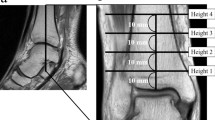

Based on past studies, with clearly defined anatomic structures of the tarsal tunnel as mark, two reference lines were set as shown in Fig. 1. Line A was a horizontal line that passed the tip of the medial malleolus18. Line B, with a width of 1 cm, was a line from the tip of the medial malleolus to the medial tubercle of the calcaneus11. A detailed description of the two reference lines can be found in following materials and methods section.

MM: medial malleolus. MTC: medial tubercle of the calcaneal. The blue horizontal line is Line A, which crosses the tip of the medial malleolus. The green oblique line (band) is Line B, with a 1 cm width, which spans from the tip of the medial malleolus to the medial tubercle of the calcaneus. This axis also represents the inferior edge of the flexor retinaculum and consequently the tarsal tunnel. ① Posterior tibial tendon, ② flexor digitorum longus tendon, ③ posterior tibial artery, ④ vein accompanying the artery, ⑤ posterior tibial nerve, ⑥ flexor hallucis tendon.

After the approval of the Ethics Committee of Dalian Medical University (DMU), 60 cases of 30 cadavers (left and right sides), which were donated through the Body Donation Center of DMU, were dissected in the Department of Anatomy of DMU. All methods were performed in accordance with the relevant guidelines and regulations established by the Ethics Committee. The age and gender distribution are shown in Table 1. Each foot was placed in the anatomical position that foot and the leg with an angle of 90 degree to standardize the measurement and image acquisition (Fig. 1). First, skin and adipose tissue of the medial foot were removed. Second, the flexor retinaculum was removed from the medial malleolus to the medial calcaneal tubercle. Finally, the posterior tibial nerve, posterior tibial artery and their branches were fully exposed.

A horizontal line that passed the tip of the medial malleolus (this is a point that is easily touched during biopsy) was regarded as reference Line A18. The distance from the bifurcation point of the posterior tibial nerve and that of the posterior tibial artery to the horizontal line were measured. The number of medial calcaneal nerves and the distance from origination points to the previous reference line were recorded. The data of the medial calcaneal artery were recorded and measured in the same way. Data distal to the reference line were recorded as negative, and data proximal to the reference line were recorded as positive.

Reference Line B with a 1 cm width was established from the tip of the medial malleolus to the medial tubercle of the calcaneus11, which was the lower boundary of the tarsal tunnel.